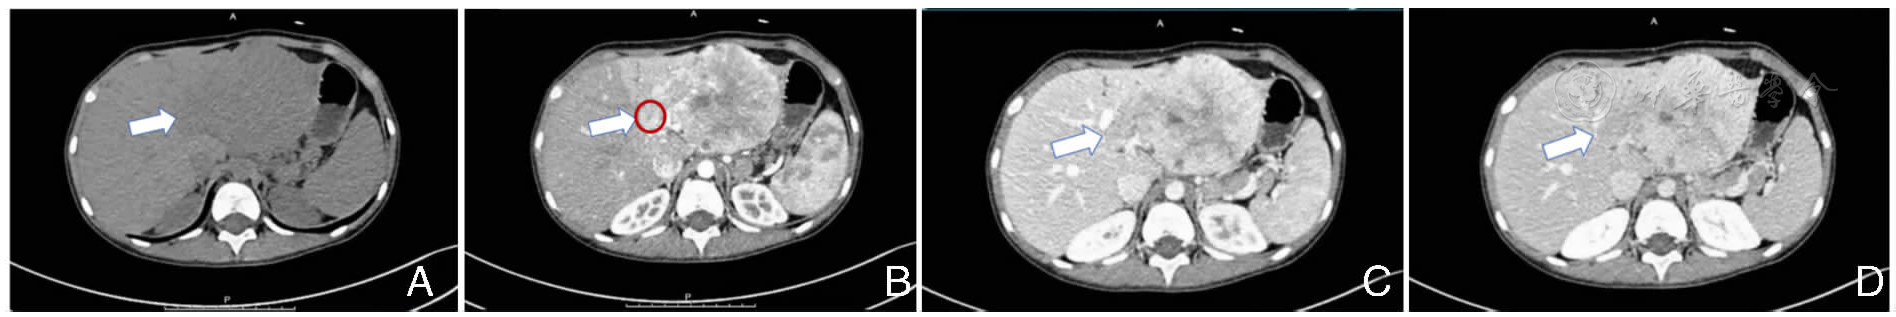

图1 腹部增强CT注:A.平扫可见肝左内叶团块低密度灶;B.动脉早期见肿瘤不均质强化,中央放射状低密度影;可见左肝管癌栓(红色圈);C.门静脉期见肿瘤强化减退,中央区放射状低密度影;D.门静脉延迟期肿瘤呈轻度强化,中央区放射状低密度影